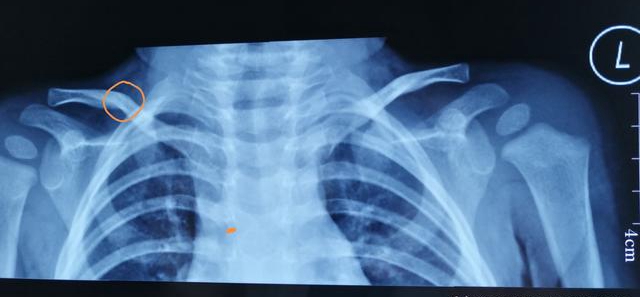

如果姥姥带着皮皮到专业的小儿骨科门诊就诊,通过问诊后医生会轻轻的按压一下锁骨,伴随而来的就是宝宝的剧烈哭闹,医生会给宝宝开具肩部正位的x线检查。

很奇怪,皮皮的x线上没有明显的表现,放射科医生给的报告上说“未见明显骨损伤”,是不是医生的判断出了问题?

但是,皮皮的锁骨压痛的表现肯定是空穴来风(你也可以说不是~~~~),是有原因的。细心如准备行囊的老母亲的小儿骨科医生不会错过任何细微的痕迹。通过仔细查看片子,可以看到,锁骨中间部位的骨皮质有微小的不连续。对,这就是锁骨骨折的x线表现。

皮皮自从就诊后都没有来复诊过,突然有一天,皮皮姥姥带着皮皮大喊着进了诊室“大夫,快看,我外孙这里怎么长了一个大包?硬硬的,不会是肿瘤吧?”让皮皮姥姥更加恼怒的是接诊的任医生很是淡定,就说了一句话“嗯,这是锁骨骨折愈合产生的骨痂,不用担心”。“怎么能不担心呢?长这么大一个包。赶紧给孩子做个检查看看。”正好也到了该复查的日子了,任医生开了锁骨正位片。不到一个小时,结果出来了,果然不出所料。看着锁骨周围像是一层干裂的泥巴样的骨痂,皮皮姥姥终于松了一口气。